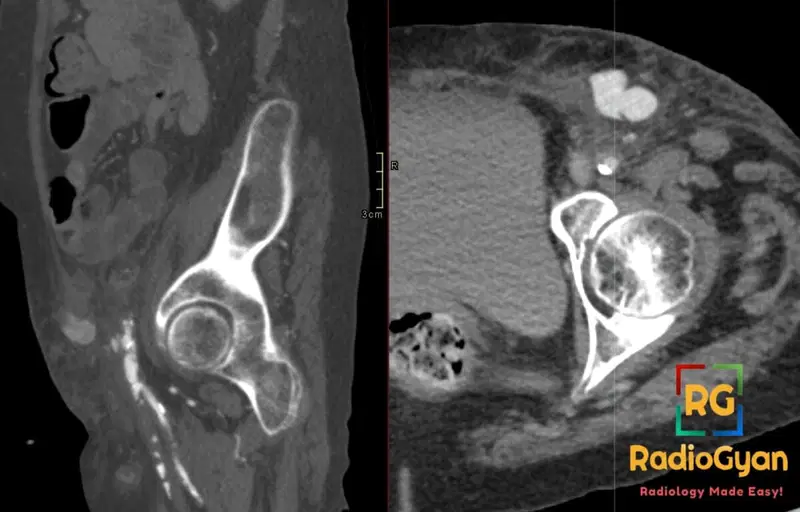

65 yr male with a groin mass following a catheterization procedure.

Diagnosis: Femoral artery pseudoaneurysm post femoral access for coronary angiogram.jpg

- CT: Contrast-enhanced CT/CTA detects saccular pseudoaneurysm as rounded/ovoid contrast-filled collection adjacent to artery with narrow neck/stalk; unenhanced shows hematoma-like mass; assesses extent, surrounding induration, atherosclerosis, and vessels.